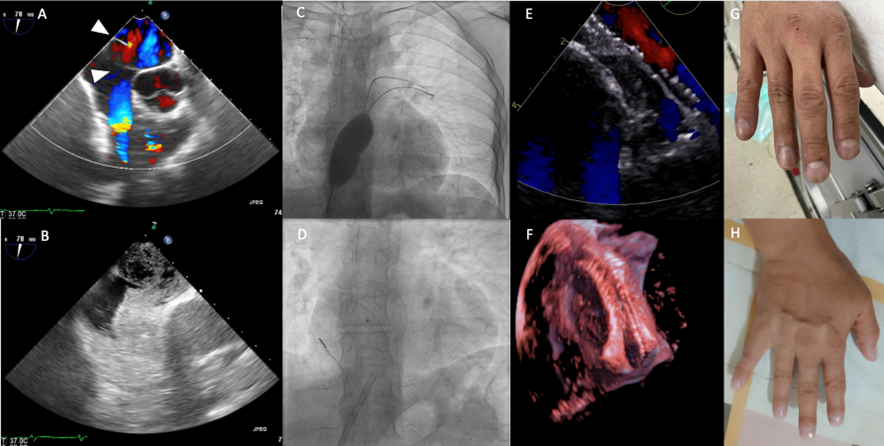

A 37-year-old man was referred to our medical center with a diagnosis of Eisenmenger syndrome due to an atrial septal defect (ASD). At admission he had central cyanosis, acrocyanosis, and progressive effort dyspnea; his symptoms improved during lying position. Physical examination revealed cyanosis, clubbing, a pulmonic systolic murmur II/IV, and SO2 between 50% and 60% on standing position and between 84% and 88% on lying position. Blood tests showed erythrocytosis (hemoglobin 20g/dL, hematocrit 60%). Transthoracic echocardiography (TTE) and transesophageal echocardiography (TEE) showed a bidirectional with predominantly right-to-left shunt ASD of 24 mm with a spiral septum and proper rims for percutaneous closure, and normal pulmonary pressure (Figure 1A and B, Videos 1 and 2). Right heart hemodynamics demonstrated a systolic pulmonary artery pressure of 17 mm Hg, a right atrium pressure of 4 mm Hg, and a Qp/Qs ratio of 1.8:1.

A balloon occlusion test (BOT) was performed using a 35-mm Occlutech sizing balloon (Figure 1C). Using the stop-flow technique, the ASD was measured at 25 mm. Pulmonary and systemic pressure showed no changes after 15 minutes. The aorta blood gas analysis improved from 88% to 97% at room air. We decided first to close the ASD with a 27-mm Figulla Flex II Septal Occluder (Occlutech); however, due to the spiral septum, it was impossible to attach it to both sides of the septum. Finally, the ASD was sealed by deploying a 33-mm occluder (Figure 1D). Six months postoperative, the patient is asymptomatic and has stopped using oxygen, oxygen saturation is on 95% without supplementary oxygen, hemoglobin is 13.4g/dL, and TTE shows no residual shunt (Figure 1E and F).

Platypnea-orthodeoxia syndrome is a rare condition that in most cases is related to a large patent foramen ovale.1,2 This is a case where an ASD with spiral septum promoted a large right-to-left shunt. We demonstrate the usefulness and feasibility of a BOT3 for the closure decision, with excellent outcomes and reversal of cyanosis, erytrhocytosis, and clubbing (Figure 1G and H).